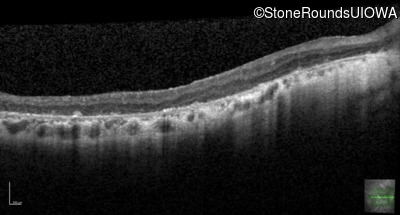

Visit at age: 35 years

Optical Coherence Tomography - Left - 20/70

Exemplar / OCT Stack